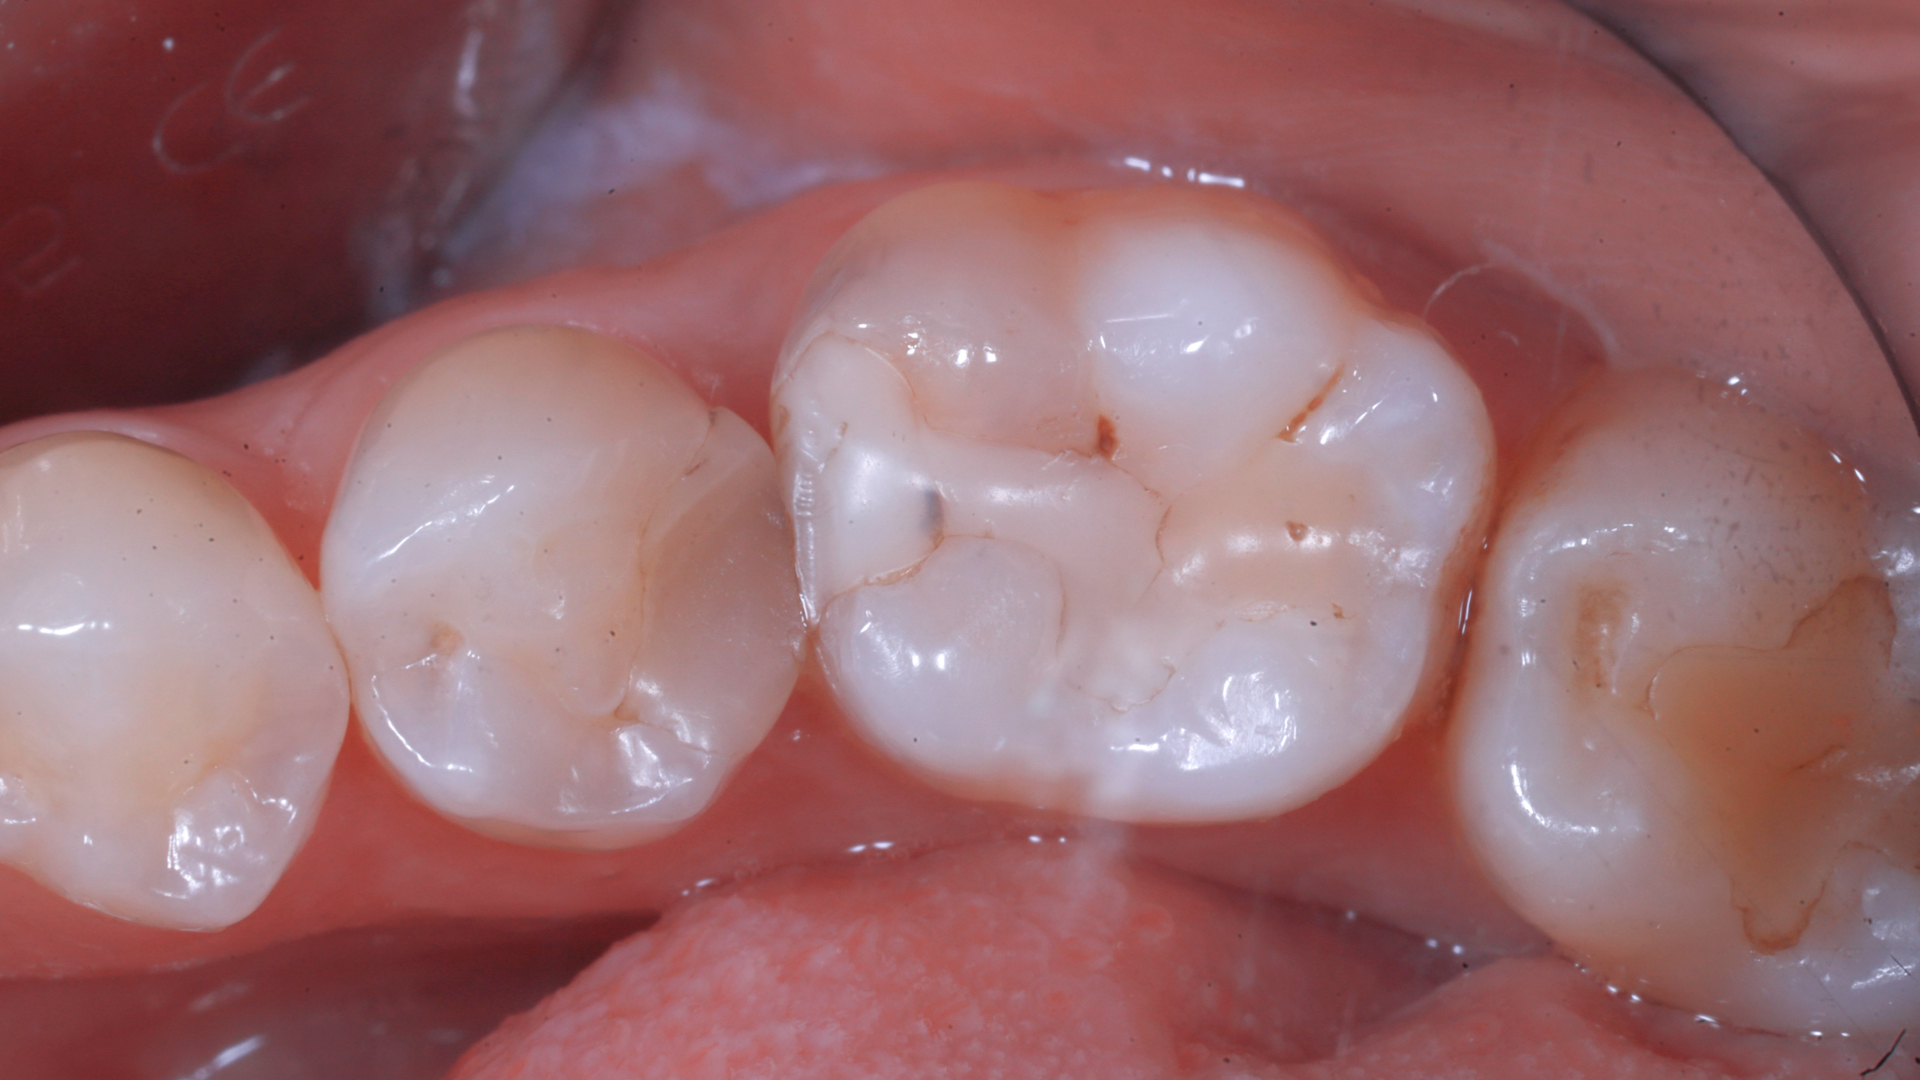

Radiografia bitewings iniziale che mostra un precedente restauro infiltrato mesiale a 2.6 ed un restauro debordante distale a 2.5Fotografia occlusale iniziale pre-opertoria